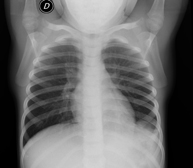

- Chest X-ray

A chest X-ray uses a small dose of radiation to obtain a two-dimensional image of the thoracic cavity and its contents (lungs, heart, mediastinum, etc.). It is one of the most commonly performed medical tests.